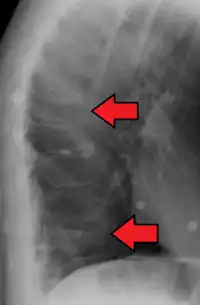

| Example of vertebral compression fracture. | |

A compression fracture is a collapse of a vertebra. It may be due to trauma or due to a weakening of the vertebra (compare with burst fracture). This weakening is seen in patients with osteoporosis or osteogenesis imperfecta, lytic lesions from metastatic or primary tumors,[1] or infection.[2] In healthy patients, it is most often seen in individuals suffering extreme vertical shocks, such as ejecting from an ejection seat. Seen in lateral views in plain x-ray films, compression fractures of the spine characteristically appear as wedge deformities, with greater loss of height anteriorly than posteriorly and intact pedicles in the anteroposterior view.[3]

Compression fractures are usually diagnosed on spinal radiographs, where a wedge-shaped vertebra may be visible or there may be loss of height of the vertebra. In addition, bone density measurement may be performed to evaluate for osteoporosis. When a tumor is suspected as the underlying cause, or the fracture was caused by severe trauma, CT or MRI scans may be performed.